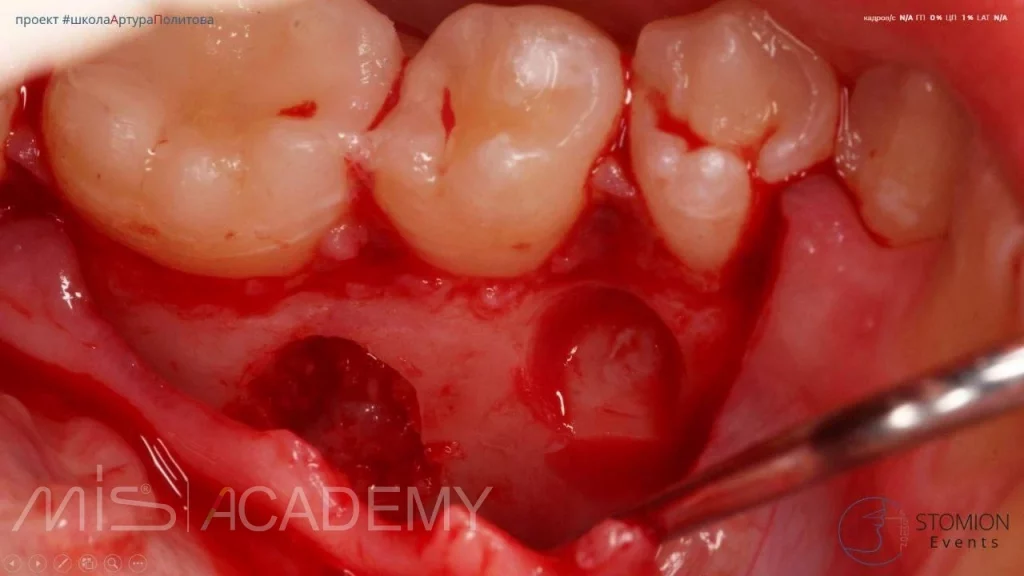

Удаление сверхкомплектных зубов

- И вот мы обнаруживаем через 4 года ещё 7 сверхкомплектных )) и 4 зачатка восьмых по рекомендации ортодонта тоже под удаление.

Одна операция, удаление всех зачатков. Скорость и безопасность продиктованы использованием навигационных шаблонов для удаления. Кстати в 2017г. тоже по навигации удалял ему зубы. Это позволило делать быстро, уверенно, безопасно.